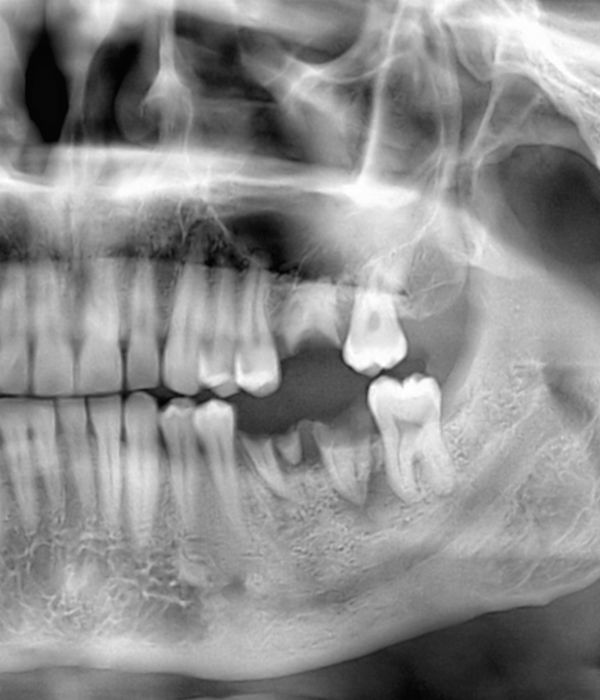

Tooth Extraction

Tooth extraction may be recommended to remove severely infected and damaged teeth or to create space in a crowded mouth. An infected tooth can sometimes be preserved through root canal therapy, but if the infection is too severe for effective treatment, the tooth may require extraction.